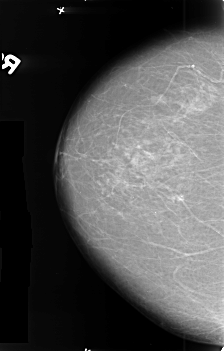

B_3412_1.LEFT_CC

LEFT_CC LINES 4608 PIXELS_PER_LINE 3120 BITS_PER_PIXEL 12 RESOLUTION 50 OVERLAY

FILE: B_3412_1.LEFT_CC.OVERLAY

TOTAL_ABNORMALITIES 1

ABNORMALITY 1

LESION_TYPE MASS SHAPE ROUND-IRREGULAR-ARCHITECTURAL_DISTORTION MARGINS SPICULATED

ASSESSMENT 5

SUBTLETY 5

PATHOLOGY MALIGNANT

TOTAL_OUTLINES 1

BOUNDARY